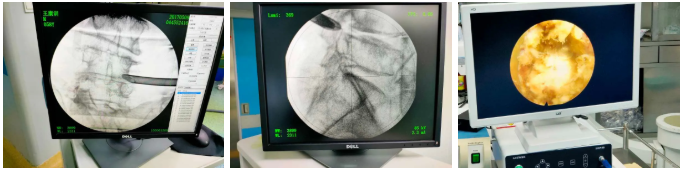

术后影像:

椎间孔镜技术,是一种方兴未艾的微创手术方法,在治疗椎间盘突出、腰椎管狭窄症等治疗中常见常用。于治强主任这两个病例采用椎间孔镜技术治疗,取得相当不错的疗效。